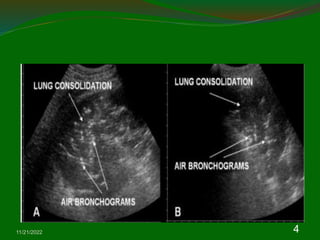

Consolidation

 Irregular hypoechic area of varying size and

shape.

 Echotexure can appear homogenous or

inhomogenous.

 The most common sonographic feature is the

air bronchogram which is characterized by lens

shaped internal echoes within hypodene area

or echogenic lines.

Summarizing sonographic

finding in consolidation

 Liver like in early stage

 Air bronchogram

 Fluid bronchogram

 Blurred and serrated margin

 Reberberation echoes in the margin

 Hypoechoic abscess formation